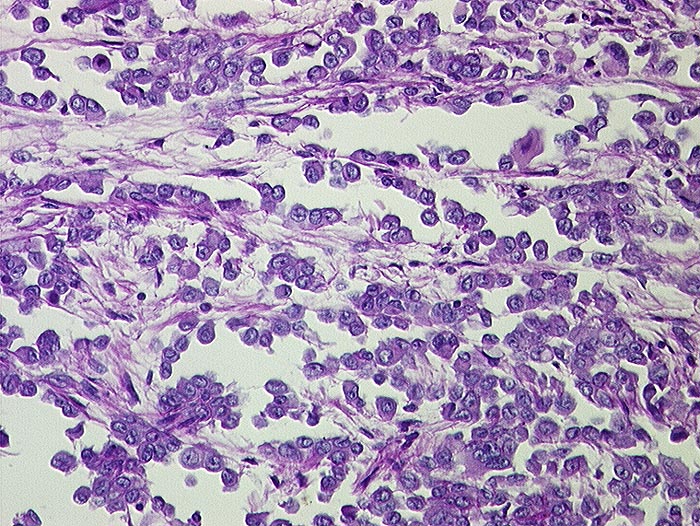

Entscheidend für die Diagnose eines malignen Mesothelioms sind maligne Zellen, die aussehen wie Mesothelzellen. Typisch ist ein Kontinuum von gutartigen, abnormen und malignen mesothelialen Zellen. Die Tumorzellen bilden polyzyklisch begrenzte papilliforme Verbände oder sitzen einem homogenen Matrixkern auf. Zellkannibalismus und lange Zellketten (Indian Files) sind häufig bei Mesotheliomen und selten in gutartigen Ergüssen. Die einzelnen malignen Zellen sind grösser und variabler als gutartige Mesothelien. Oft trifft man auf grosse und mehrkernige Tumorzellen. Das Zytoplasma von Mesotheliomen ist auffallend dicht ,anders als das eher helle Zytoplasma von Adenokarzinomen.